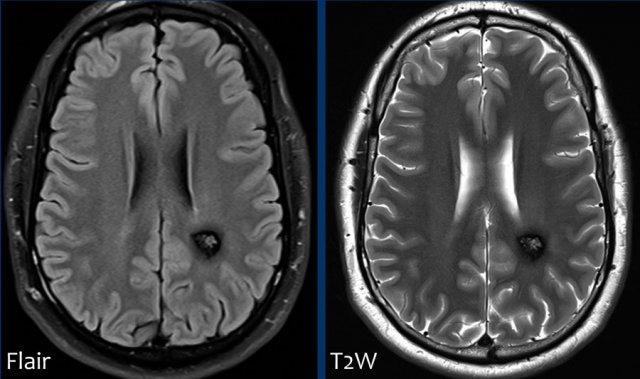

Các ổ xuất huyết nhỏ này còn được gọi là xuất huyết vi thể (microbleeds).

Lưu ý số lượng rất nhiều các ổ xuất huyết nhỏ này, phân bố chủ yếu ở vùng ngoại vi của não.